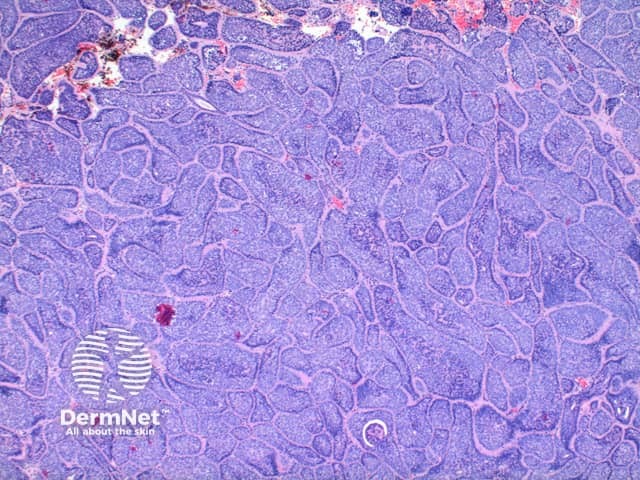

Low power view of cylindroma shows a non-encapsulated tumour nodule arising from the dermis (Figure 1). This is formed by multiple irregular tumour islands, distributed in an aptly named ‘jigsaw’ pattern (Figure 2). Surrounding the tumour islands, and in discrete droplets within the nodules is a thick hyaline deposit (Figure 3). Two populations of cells are noted to make up the tumour nodules. A smaller cell with a hyperchromatic nucleus tending to the periphery, and larger cells with open nuclei throughout the centre of the nodules (Figure 4).

Figure 1